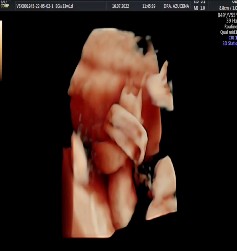

Se evidencia la presencia del signo de la soga colgante. En un corte transversal, se observa al cordón umbilical enrollado sobre sí mismo (Figura 2), formando un lazo y un bucle fijo, con un nudo que configura un lazo en el cordón umbilical, lo que sugiere la posibilidad de un nudo verdadero. Tras la aplicación Doppler color e imágenes 3D, se corroboró la sospecha diagnóstica (Figura 3).

En la búsqueda de una imagen ecográfica para apoyar el diagnóstico de esta entidad, se han descrito los signos de "la soga colgante", "bucle fijo" o "lazo de cordón", circundantes en una sección transversal de cordón umbilical, y "del ciclón"; este último promete ser altamente sugestivo e incluso patognomónico si persiste a pesar de los movimientos fetales 4. Estos signos fueron encontrados en la paciente, y ayudaron a realizar la sospecha diagnóstica, con la posterior ecografía en tres dimensiones para confirmarla.